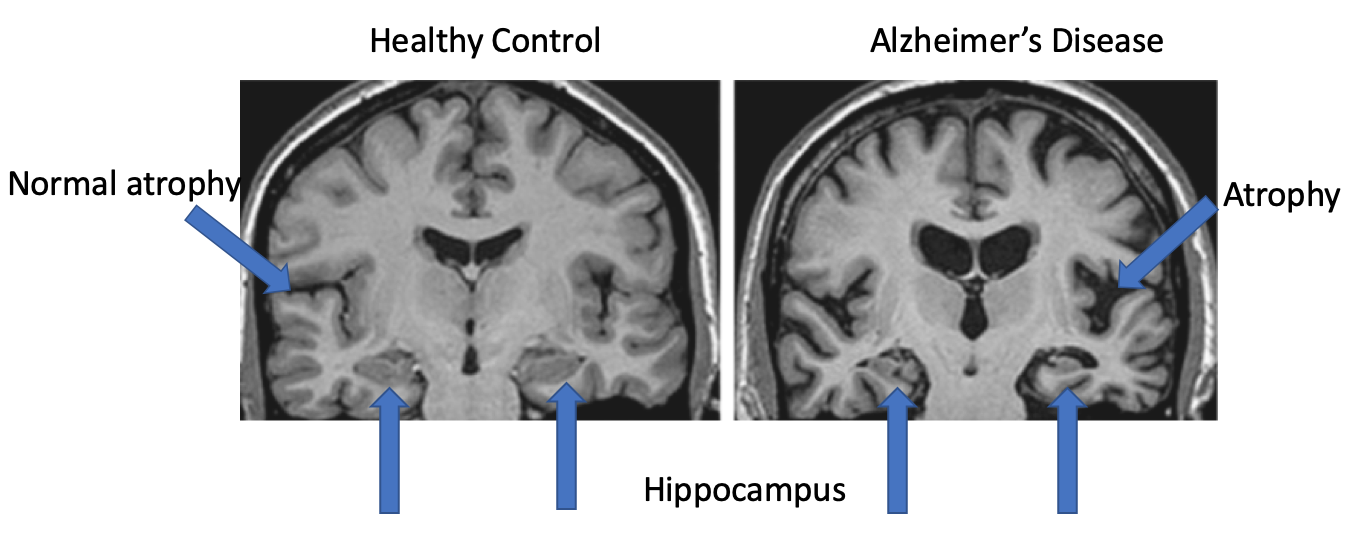

Alzheimer's Disease, MRI Brain Scan - Stock Image - C009/6590 - Science

www.sciencephoto.com

www.sciencephoto.com

alzheimer mri scan

What Can A Brain MRI Tell Us About Dementia? - MRI Chandigarh

mrichandigarh.com

mrichandigarh.com

MRI Scan Of Brain – Alzheimer’s Disease – Dementia Services Information

dementia.ie

dementia.ie

What Can A Brain MRI Tell Us About Dementia? - MRI Chandigarh

mrichandigarh.com

mrichandigarh.com